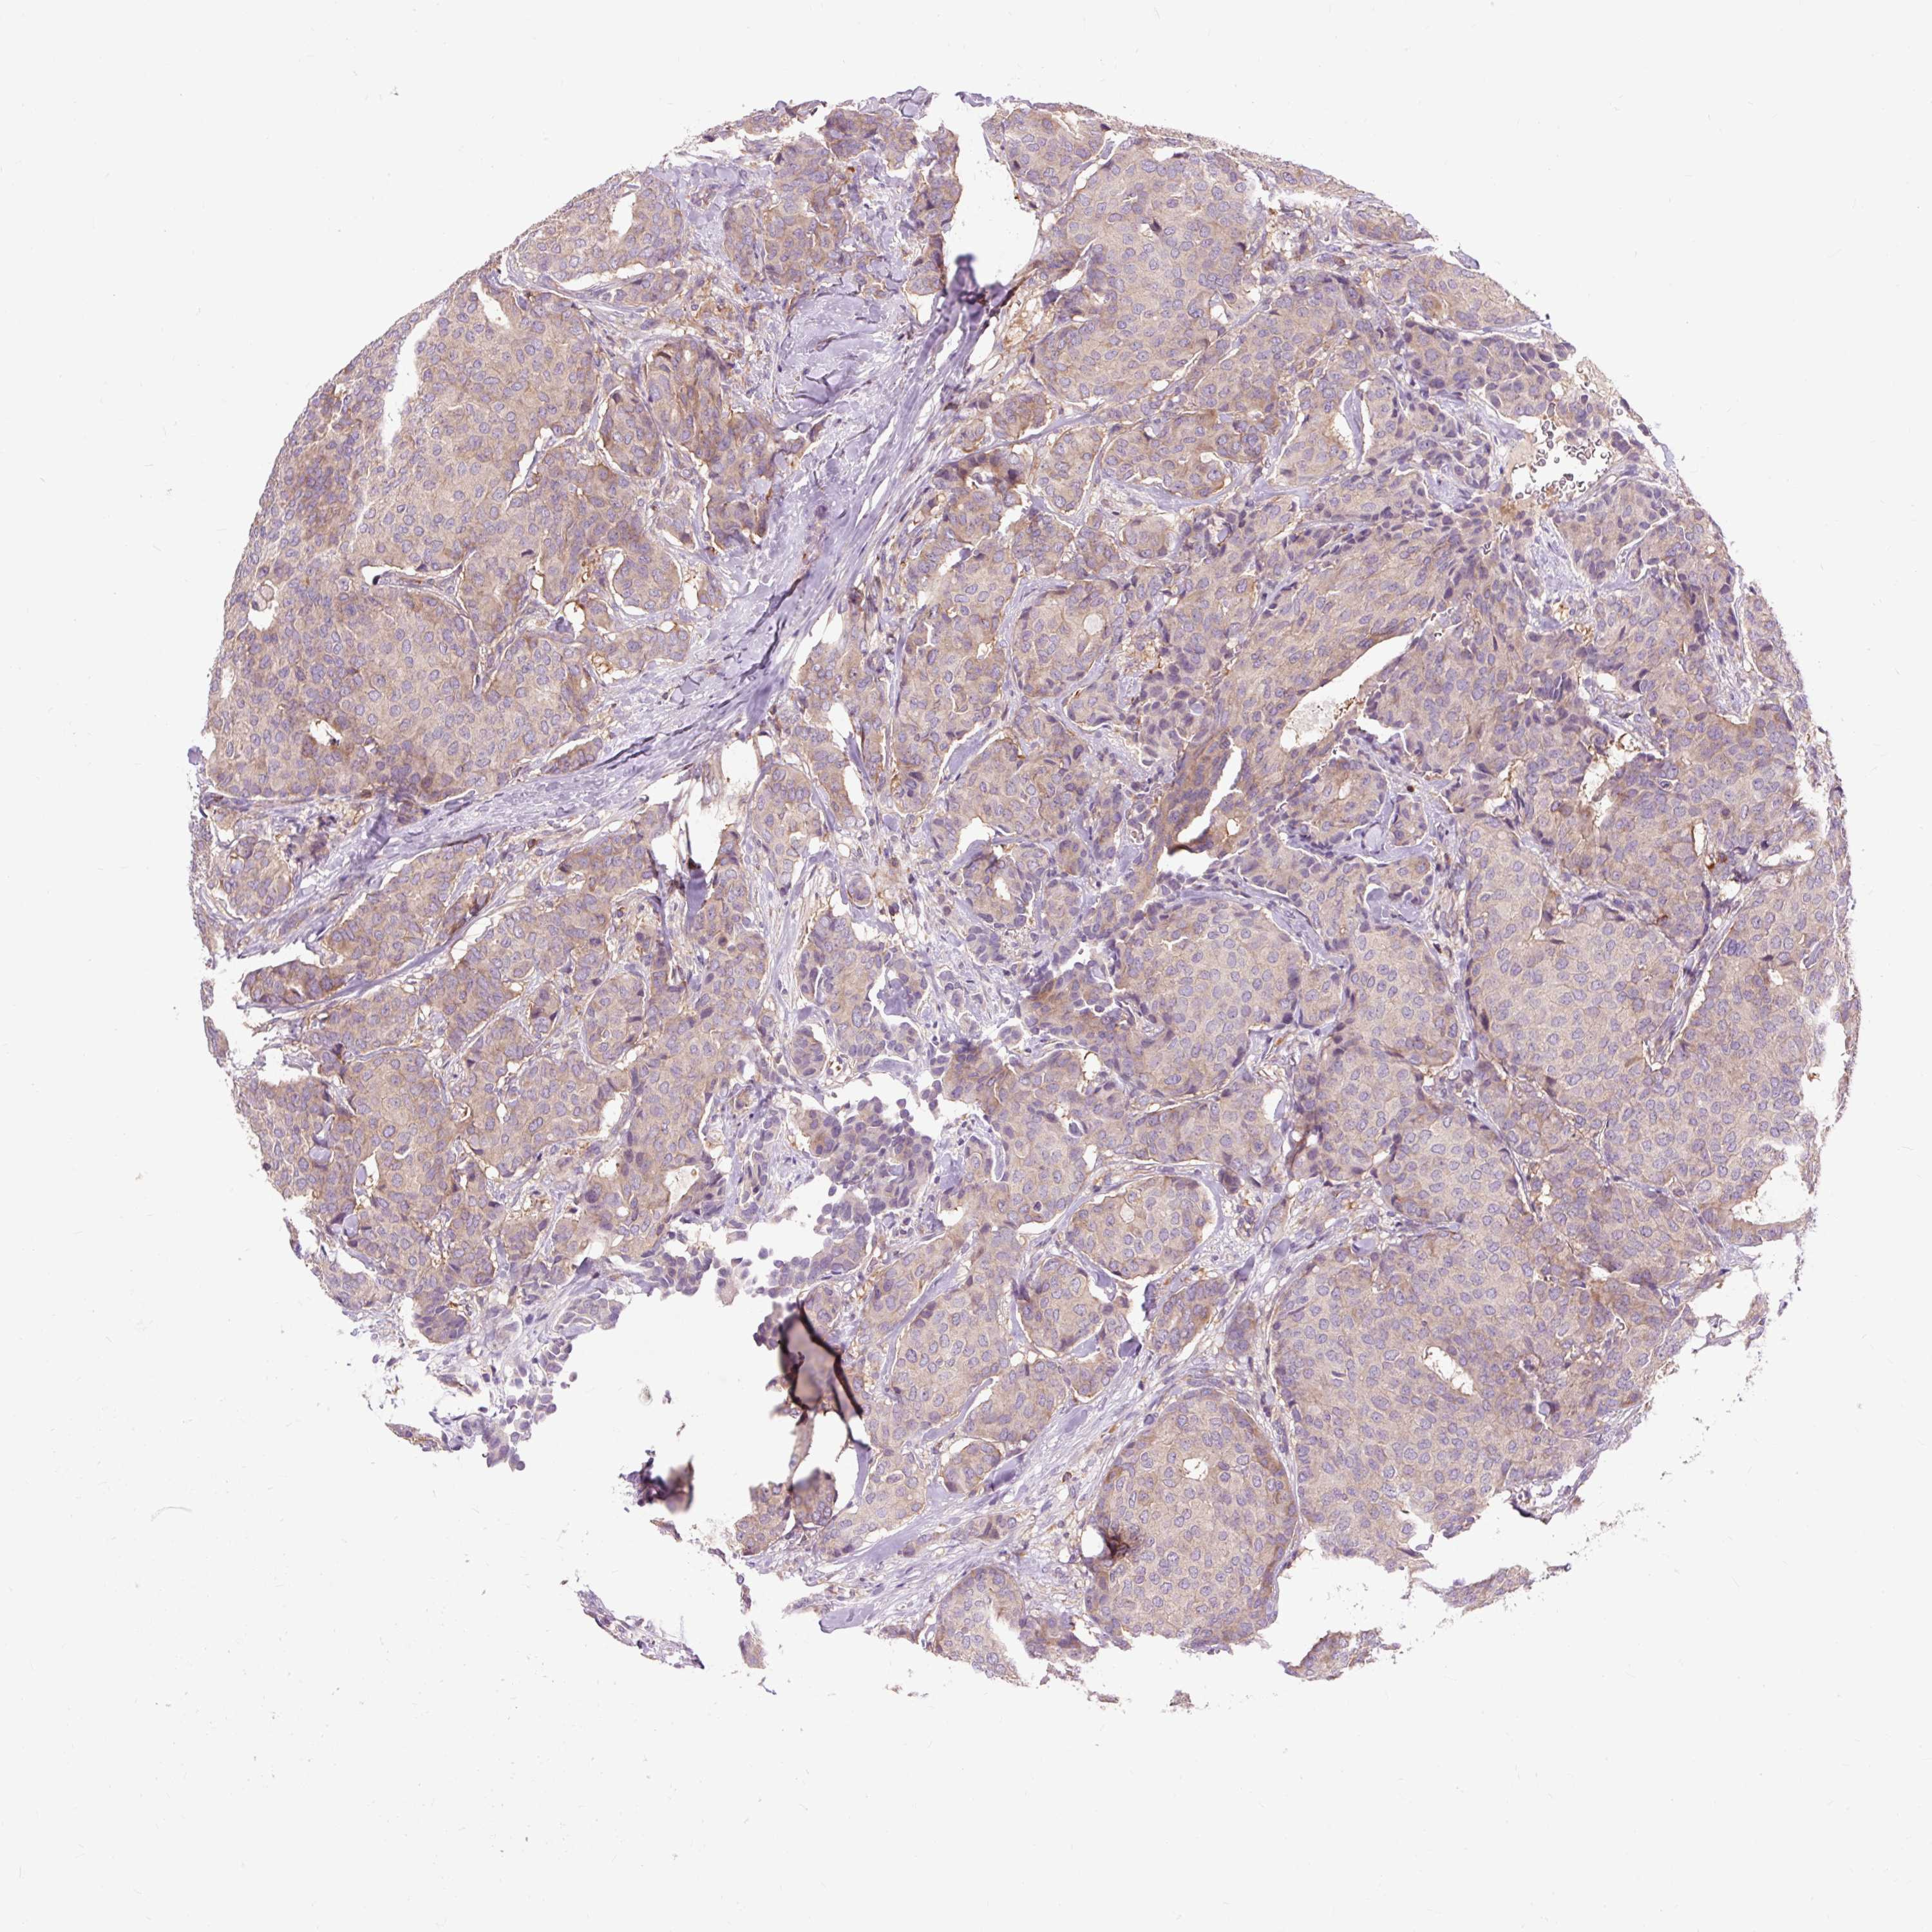

CANCER BREAST CANCER Show tissue menu

BRCA TCGA BRCA VALIDATION PROTEIN EXPRESSION